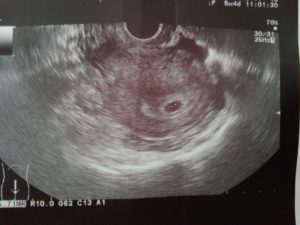

Расшифровкой данных ультразвукового исследования должен заниматься только квалифицированный специалист. На первом УЗИ специалист определяет:

- Наличие каплевидного или округлого гипоэхогенного образования, диаметр которого составляет 0,3-0,5 см. От срока зависит и размер.

- Образование должно быть окружено тонкой оболочкой. Данное образование и есть плодное яйцо.

- Наличие желтого тела.

Во время первого УЗИ обнаруживаются:

- круглое или каплевидное образование с низкой эхогенностью размером 3-5 мм. Его размер определяет срок;

- тонкая оболочка вокруг развивающегося ребёнка;

- жёлтое тело – оно вырабатывает прогестерон, способствующий сохранению плода.